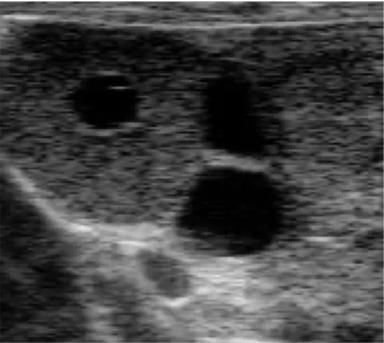

Кисты яичника у КРС

1,04К

Добрый день коллеги, рад вернуться сюда снова!

Итак, сегодня предлагаю к обсуждению такую проблему как кистозная дегенерация фолликулов яичника, в простонародье - кисты .

Они ...

Возвращаясь к Вашему комментарию, соглашусь по поводу 3го случая, он очень спорный и разные специалисты будут его трактовать по разному.

И касательно этого снимка, я согласен что также (как трабекулы) могут светиться лизированные эритроциты, полость обычно схлопывается и заростает через 20-30 дней, (около 90%).